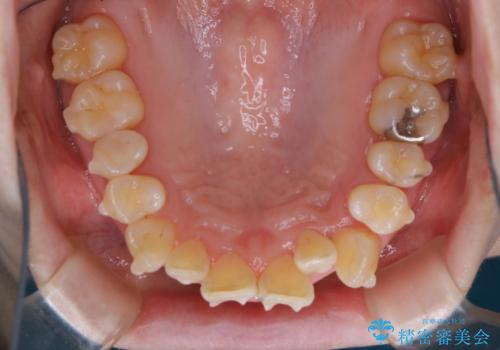

- インビザラインでのマウスピース矯正中に、歯の黄ばみが気になるため綺麗に白くしたいとのことでした。PMTC60分コースを行いました。

PMTC(保険外治療)は、毎日の歯磨きで落としきれない汚れや、コーヒ、紅茶・タバコのヤニなどの着色も除去します。目には見えない歯と歯の間・歯肉の境目・インビザライン中はアタッチメント周囲などに残っているプラーク(歯垢)もしっかり取り除きます。PMTCでは専門的な機械や材料を使用して、徹底的に汚れを除去するため、虫歯・歯周病・口臭予防などにつながります。

またPMTCを行うことで、ご自身本来の歯の色になり自然な明るさになります。